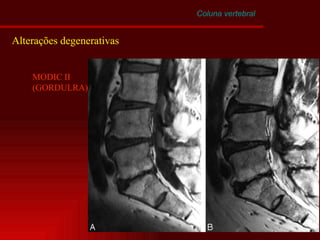

Coluna vertebral Alterações degenerativas MODIC I = agua

Coluna vertebral Alterações degenerativas MODIC II (GORDULRA)

Coluna vertebral Alterações degenerativas MODIC III =FIBROSE